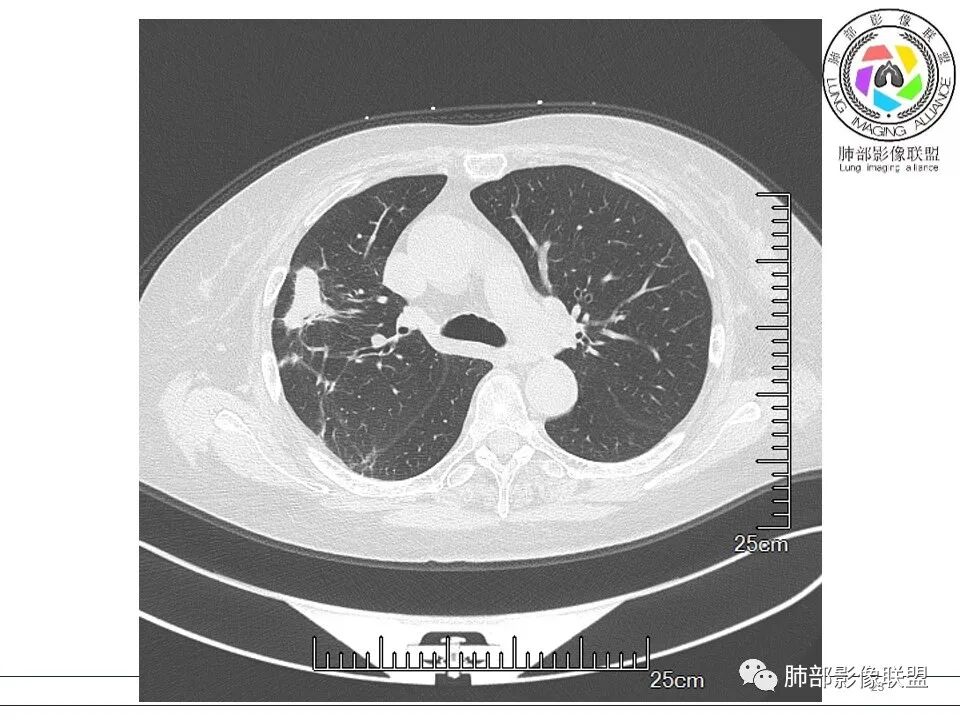

红日初升: 胸膜下结块,平行胸膜,收缩力较强,肉芽肿样边缘,考虑炎性,小卫星灶、似有凝固性坏死,隐球>op

金豆 (刘权威): 右肺上叶胸膜下团块,支气管充气征,边缘纤维索条,磨玻璃,OP。

衡妈: 老年女性,右肺上叶沿胸膜下不规则实性病灶,长轴平行于胸膜,有结节融合感,边缘部分彭隆部分平直,周围可见数条纤维灶影,病灶内可见充气支气管征未达远端,首诊考虑慢性炎性肉芽肿,隐球菌?机化性肺炎?建议增强扫描及ct下穿刺活检。

张延军: 病变与胸膜平行,近端见气管进入,口服激素治疗史 考虑隐球菌感染 伴OP样改变

良孑: 右肺胸膜下多发结节,长轴与胸膜平行,部分病灶有多结节融合,可见近端支气管充气征,有晕征及晕中软毛刺,长期口服激素病史,抗炎效果欠佳。病灶形态单一,无播散性树芽,结节内无支气管穿行,单侧发病,收缩力差,可排除TB,OP及淋巴瘤,综和考虑支持隐球菌

内部支气管扩张,周围少量GGO,而且病灶离开了胸膜,附近长索条影,支持机化的改变

5、分布:隐球菌肺炎是肺泡性炎症,病灶分布多位于胸膜下,可紧贴胸膜,也可与胸膜邻近,病灶长轴与胸膜平行。(划重点,分布特点非常重要,因为隐球菌如果没有荚膜,会被巨噬细胞吞噬,在人体内是无法生存。隐球菌孢子吸入后,要有高浓度的CO2的条件下,才能形成荚膜,所以肺泡内、胸膜下多见)

8、晕征:病变早期可出现磨玻璃晕征,为周围炎性渗出或肺间质受累。

11、收缩力:可以较弱,也可以较明显伴有胸膜牵拉。